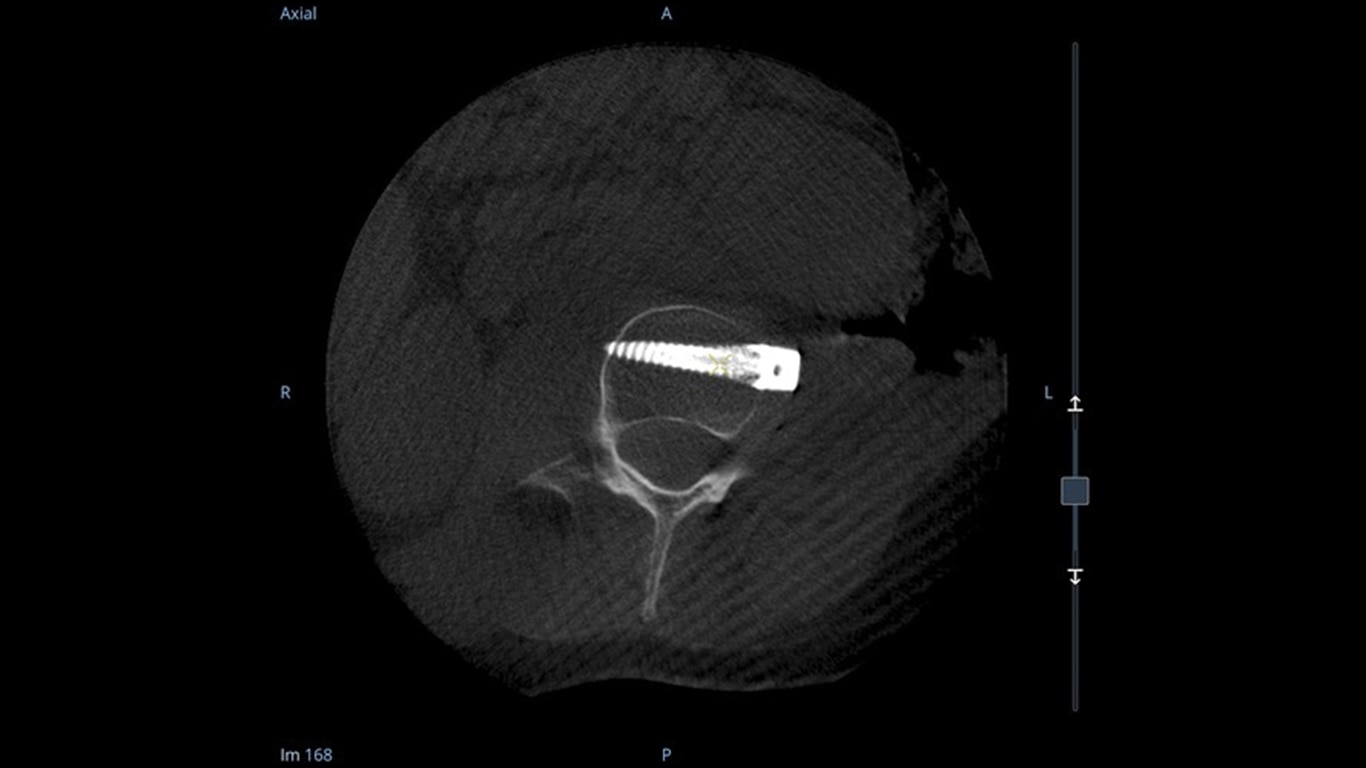

Mehr sehen, schneller entscheiden: Der OEC 3D ermöglicht die gleichzeitige Darstellung mehrerer Ebenen bei verschiedensten Anwendungen. Ob Spondylodesen, komplexe Trauma- Chirurgie oder Bronchoskopien. Mit einem Volumen von 19 × 19 × 19 cm liefert er bis zu 67 % mehr Bildinformationen als vergleichbare Systeme – für mehr Sicherheit und Effizienz im OP.

Analysieren Sie Ihre Scans mit dem GE Volume Viewer – genauso intuitiv wie am CT. Profitieren Sie von der vollständigen Darstellung axialer, koronarer und sagittaler Ebenen sowie von MIP-Ansichten und 3D-Visualisierungen im VR-Modus. Scrollen Sie durch bis zu 512 Schichten mit nahtloser Anpassung der Schichtdicke – für eine präzise Befundung direkt im OP.